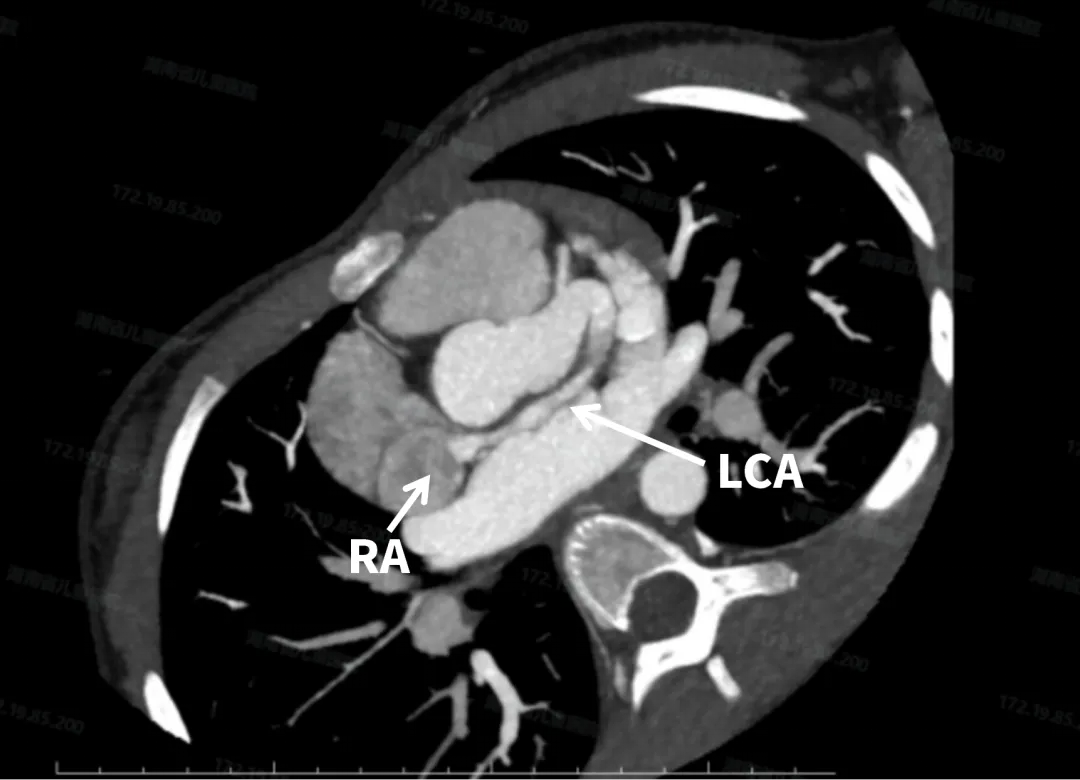

术前CT检查

左冠状动脉主干增粗明显,左回旋支向右发出一支血管前走行汇入右心房。

本例患者术前CT显示左冠状动脉主干增粗明显,最宽约15.2mm,左回旋支向右发出一支血管前走行汇入右心房,粗约6.2mm,最终诊断为左冠右房瘘。而长期大量左向右分流导致肺血流量增加、右心室容量负荷加重,最终可引发右心衰竭。同时,患者已出现冠状动脉显著增宽伴瘤样扩张症状,瘤体内易形成血栓,血栓脱落可致远端栓塞或心肌梗死。根据JACC最新综述,源自左回旋支汇入冠状窦的瘘管具有进展为大型CAF的趋势,明确诊断后应尽早关闭[2],判定符合手术指征。